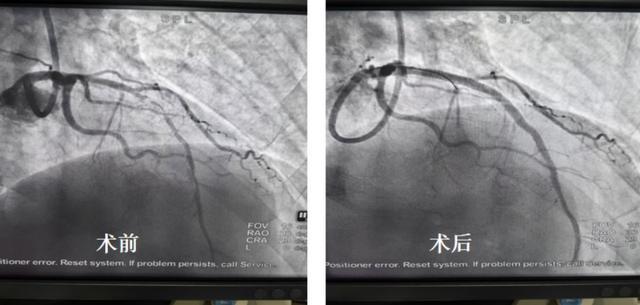

本例患者因左前降支近段严重钙化狭窄,在当地医院尝试常规介入治疗失败,每日胸痛发作频繁,只要下地走路就会诱发胸痛,生活受到严重困扰。接受冠脉旋磨后,血管狭窄得到有效改善,术后次日即可正常下床活动。(该患者术前、术后造影对比图)